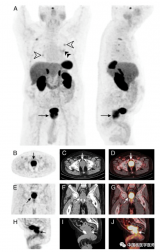

PET/CT下,良性前列腺增生摄取68Ga-DOTATATE

一名79岁的男性患有类癌综合征并发现双侧肺结节,肺结节活检证实为分化良好的神经内分泌肿瘤。随后患者接受了68Ga-DOTATATE PET/CT显像评估。MIP图显示明显摄取68Ga-DOTATATE的双侧多个肺结节(A,白色箭头)、左肺门淋巴结(A,双黑色箭头)和前列腺(A,黑色箭头)。 2022-05-16 PET/CT